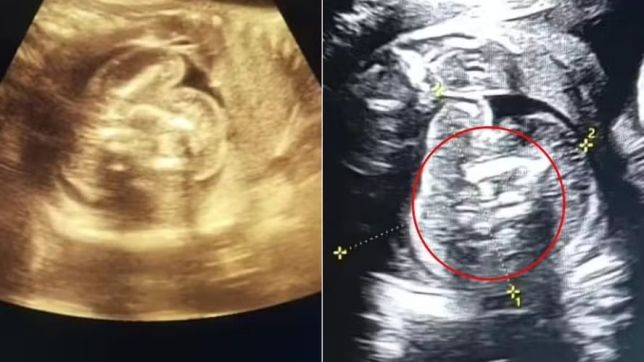

Uma mulher de 32 anos deu entrada em um hospital na Índia para um exame de rotina quando completou 35 semanas de gravidez. Embora os exames anteriores tenham dado resultados normais, os médicos descobriram que seu bebê, do sexo masculino, tinha outros dois fetos crescendo dentro dele, em um caso raríssimo.

Os especialistas disseram que havia “uma estrutura adicional contendo ossos” no abdômen do bebê. O fenômeno, apelidado de "feto dentro de feto”, só foi registrado cerca de 200 vezes na literatura médica. Não está claro quantas delas envolveram múltiplos fetos.

A mulher deu à luz seu filho em 1º de fevereiro, com cerca de 35 semanas de gravidez, e os médicos removeram os dois fetos, que pararam de crescer em algum momento da gravidez, do estômago do bebê. De acordo com relatos locais, a mãe e o bebê estão saudáveis.

"Tive sorte e fui vigilante o suficiente para notar algo muito incomum com este bebê, um feto em crescimento normal, com alguns ossos e uma estrutura semelhante à de um feto no abdômen. Imediatamente me ocorreu que isso não era normal”, explicou o médico Prasad Agarwal, que conduziu o exame.